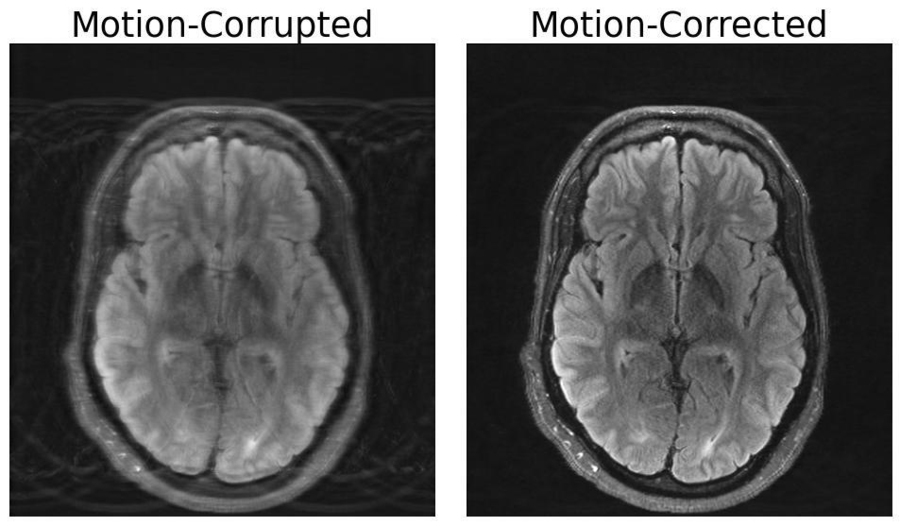

The image on the left depicts an MRI scan of the human brain corrupted by motion artifacts, whereas the image on the right depicts the same image with motion correction applied by a deep learning model developed by researchers at MIT (Credit: The researchers).

Compared to other imaging modalities like X-rays or CT scans, MRI scans provide high-quality soft tissue contrast. Unfortunately, MRI is highly sensitive to motion, with even the smallest of movements resulting in image artifacts. These artifacts put patients at risk of misdiagnoses or inappropriate treatment when critical details are obscured from the physician. But researchers at MIT may have developed a deep learning model capable of motion correction in brain MRI.